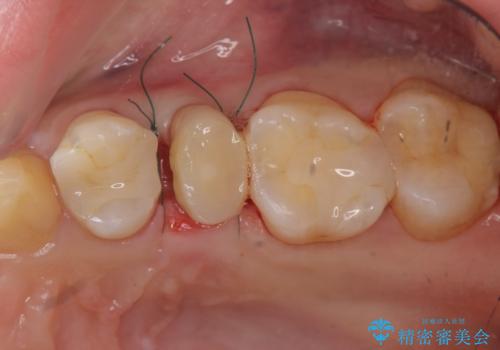

挺出小矯正を行った縁下カリエス治療

X線撮影を行い、隣接面に多発した虫歯と歯ぐきよりも深くなってしまった虫歯を小矯正をおこなったのちのセラミック治療で問題を解決します。

- 47.3万円(仮歯×3・ファイバーコア・ジルコニアクラウン×3・部分小矯正)費用は治療当時の料金となります

小矯正を行い深い虫歯を改善した後は、小手術を行うことで歯ぐき・周囲歯槽骨の状態を整えることでより安定した歯周環境を得ることができます。